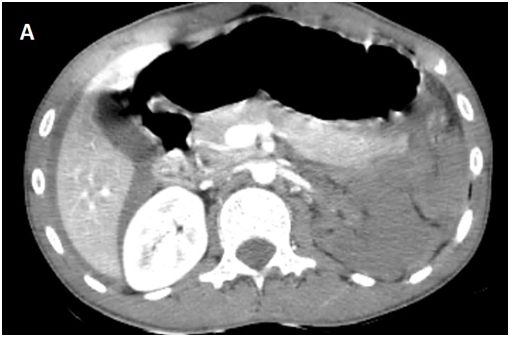

Whole body CT Scanner was performed 5hours after the accident Figure 1, which revealed a laceration fracture of the spleen responsible for a low abundant intraperitoneal hematoma, associated with left renal ischemia due to a sub intimal damage on the left renal artery wall, with formation of a secondary obstructive thrombus, in addition to a left peri-renal hematoma of 16mm, without parenchymal lesions or extravasation of contrast, otherwise ; left vein, the right kidney and his pedicle were intact.

Figure 1A Contrast enhanced CT abdominal scan.

Figure 1B Contrast enhanced CT abdominal scan.

Figure 1C Contrast enhanced CT abdominal scan.

Figure 1D Late acquisition of contrast enhanced CT abdominal scan.

laceration fracture of the spleen responsible for a low abundant intraperitoneal hematoma, associated with left renal ischemia due to a sub intimal damage on the left renal artery wall, with formation of a secondary obstructive thrombus, in addition to a left peri-renal hematoma of 16mm, without parenchymal lesions or extravasation of contrast, otherwise ; left vein, the right kidney and his pedicle were intact.

A Contrast enhanced computed tomography control was performed at D+7 showing a sudden stop of the Contrast progression at the initial portion of the left renal artery, leading to total left renal ischemia, with stability of the perirenal hematoma, spleen injury and no extravasation at the late acquisitions.